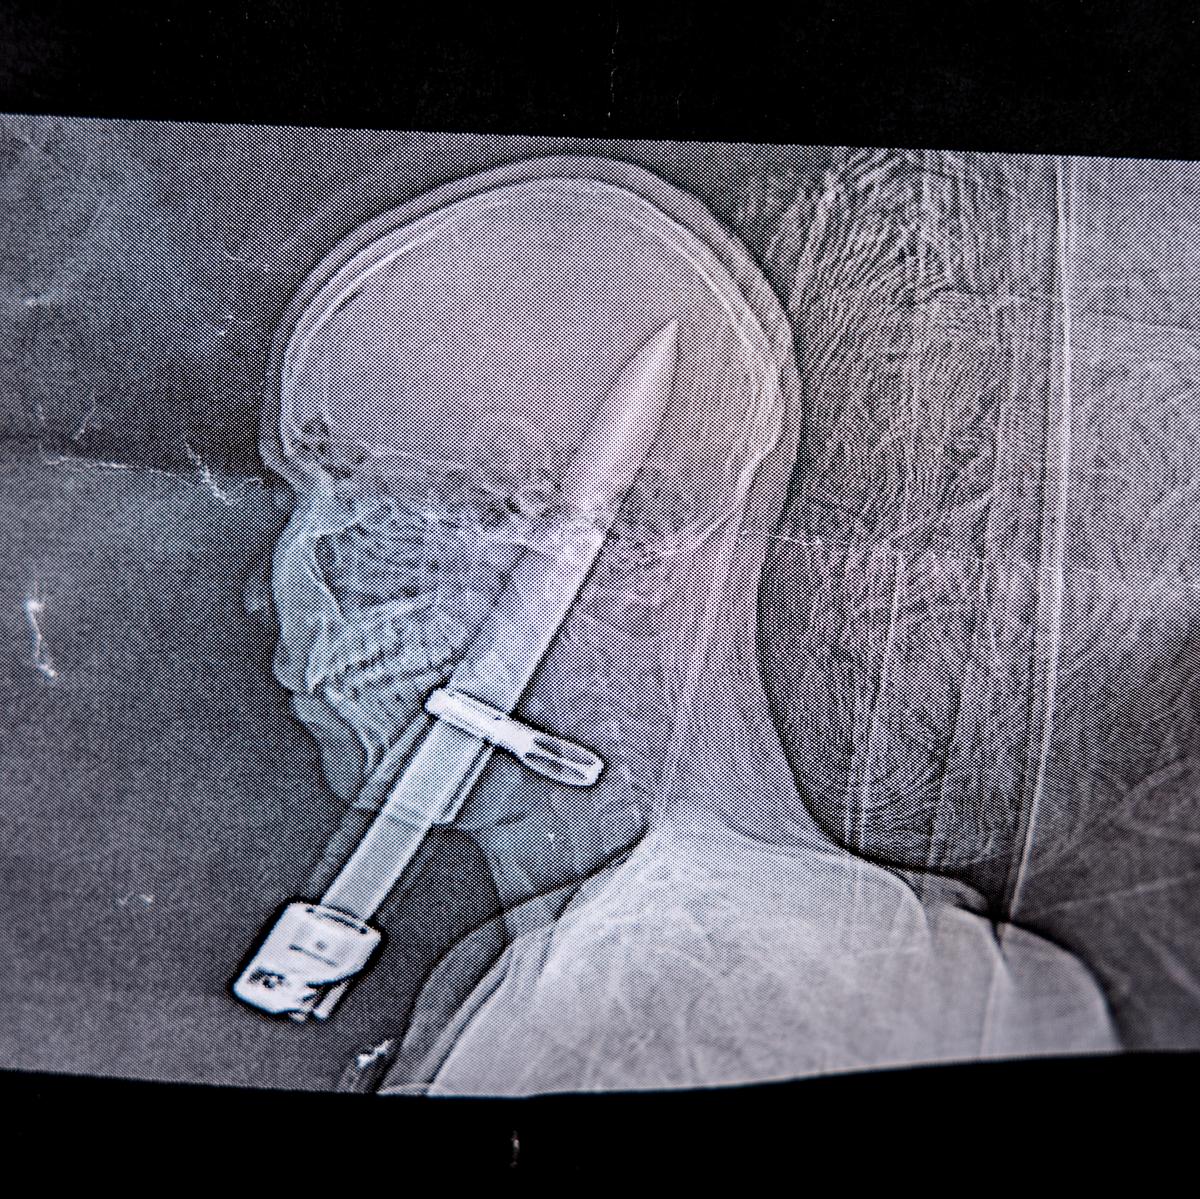

During his shift as a high guard outside the Royal Palace, Alexander Löfgren, 19, slipped and was impaled in the head by his own bayonet.

The tip penetrated twelve centimeters.

The tip penetrated twelve centimeters into the head.

Then he found out that the tip had penetrated twelve centimeters into the skull and even scratched the brain.